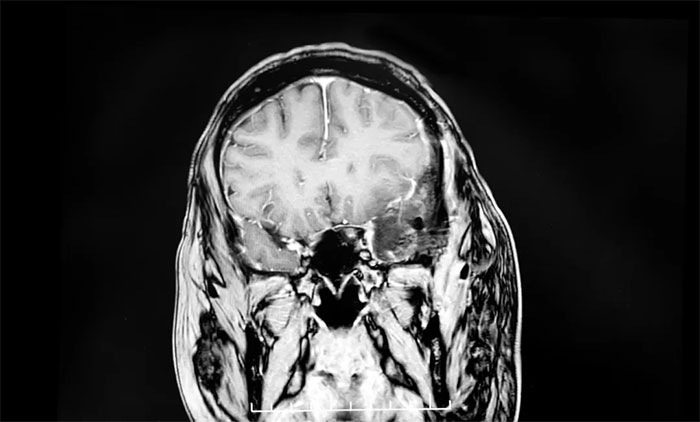

一天,李大哥从工位上起身,突然感到一阵头晕眼花,他赶紧站定缓了一缓,头晕的劲儿很快就过去了,李大哥也就没太放在心上。可没想到,头晕的症状渐渐频繁了起来,持续了一个多月还未见好。李大哥心下有些不安,决定去医院做个检查,最终查出巨大脑膜瘤。

为何脑膜瘤发现时常常很大?上海蓝十字脑科医院【同济大学附属蓝十字脑科医院(筹)】6B神经外二科副主任卢云鹤博士解释:脑膜瘤多为颅内良性肿瘤,生长缓慢。尤其在“神经功能哑区”(对早期症状不敏感的区域),患者在早期几乎没有明显不适。只有当肿瘤长到一定程度,压迫周围组织或血管,影响大脑功能时,才会出现较明显的症状。一旦症状显现,往往意味着肿瘤已无生长空间,随时可能诱发脑疝甚至呼吸心跳骤停等致命危险,必须尽快手术。

▲ 脑膜瘤早期症状较为隐匿